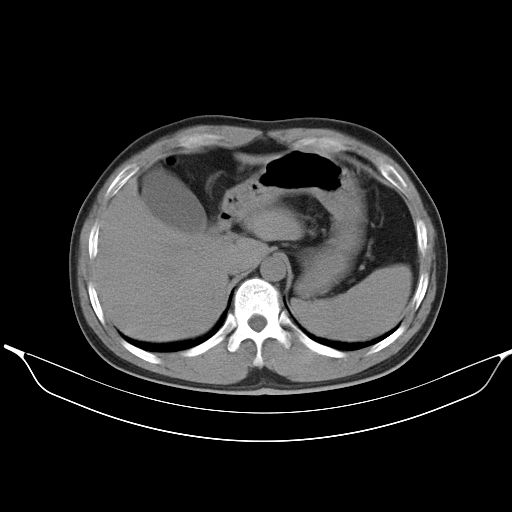

标题: CT25490:男,40岁,体检发现;无其它不适。 [打印本页]

标题: CT25490:男,40岁,体检发现;无其它不适。

考虑右下肺周围性肺癌并肺内多发转移,纵隔淋巴结转移!

支持 !考虑右下肺周围性肺癌并肺内多发转移,纵隔淋巴结转移,(气管前腔静脉后,隆突下,主动脉弓下都有了)

1、均为转移,原发灶不在肺内。2、肺癌肺转移。